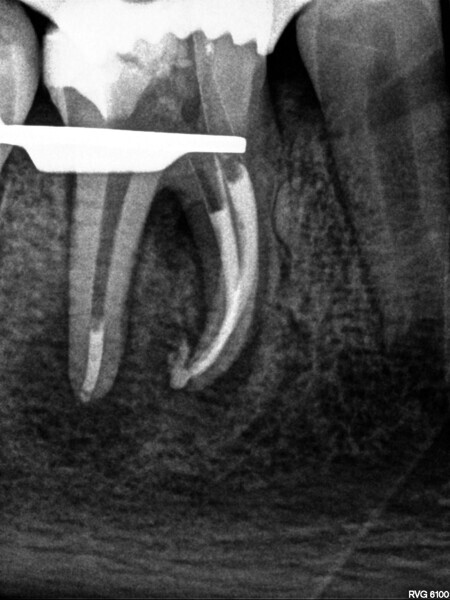

Fig. 7: Control of the obturation before final restoration.